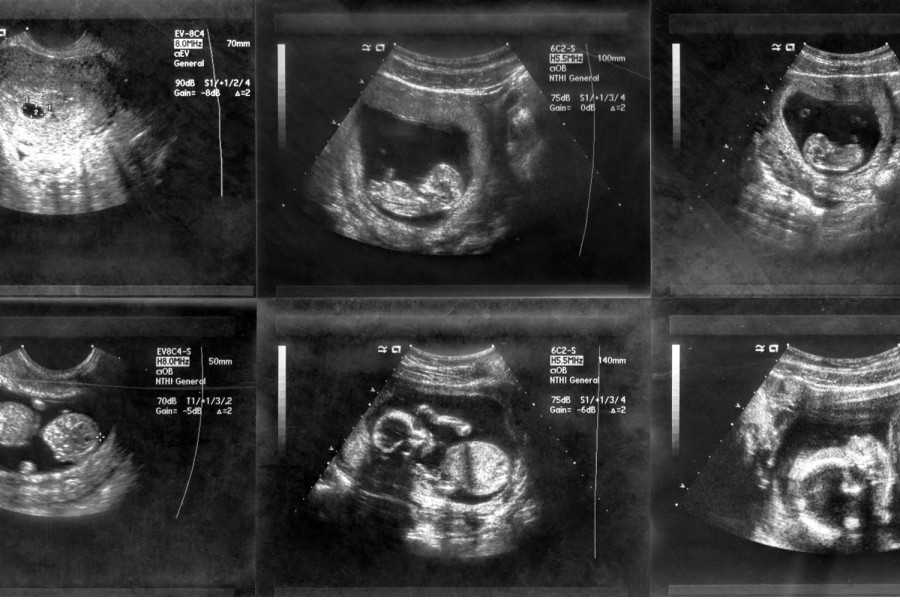

Конечно, больше всего будущим родителям интересно знать, что происходит с малышом на 8–9 неделе. Он растет, и к этому сроку беременности длина плода уже достигает 2,5 см. Это примерно небольшая виноградинка или вишенка. Он свободно расположен в полости матки. При этом вес его составляет 4 грамма. Но, несмотря на небольшие размеры, при проведении ультразвукового исследования, у малыша уже можно различить личико и половой бугорок.

Также на врач может увидеть и сообщить родителям много другой полезной информации, а также показать плод на мониторе, присоединенном к датчику УЗИ. Эмбрион на 9 неделе жизни выглядит как человек, явно различимы голова, лицо с носиком и губами, ушные раковины, тельце, ручки и ножки с маленькими пальчиками. Но у ребенка все есть небольшой хвостик, а пропорции тела далеки от пропорций взрослого человека, и даже новорожденного. Голова эмбриона гораздо больше и доминирует над телом.

На УЗИ плода на 9 неделе определяется толщина плаценты и общее состояние пуповины. При помощи допплера, будущая мама может отметить частоту сердечных сокращений малыша. Хотя многие внутренние органы уже достаточно развиты, это не всегда можно увидеть на УЗИ на 9 неделе.

УЗИ на сроке 9 недель

Плод на 9 неделе беременности и его развитие

Беременность 9–10 недель — это период очень активного развития ЦНС. Сформированы полушария головного мозга, закладывается мозжечок. Скоро движения малыша приобретут целенаправленность. Но уже сейчас он может двигать ручками, ножками, а если находится возле стенки матки — отталкивается от нее, как в бассейне. Малыш даже может совершать глотательные движения.

Продолжается формирование сердца. Сейчас оно сокращается с частотой 130–150 ударов за минуту.

У эмбриона постепенно выпрямляется спинка, исчезает хвостик. Его головка склонена к туловищу, и пока она непривычно большая. Уже сформировались глазки малыша, но пока они закрыты веками. Еще не образованы свето- и цветочувствительные рецепторы сетчатки, они образуются на более поздних сроках.